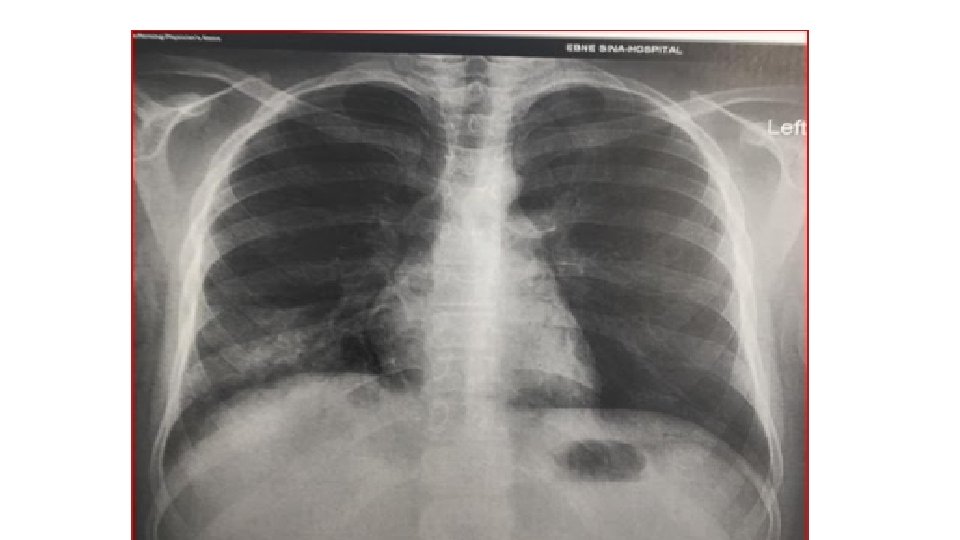

Chest X-ray An X-ray : look for signs of inflammation in chest. If inflammation is present, the X-ray can also inform about its location and extent.

In COVID-19 pneumonia Leukopenia in ~70% of hospitalized patients. LDH may be modestly elevated. LFTs elevated more commonly than in typical Community-Acquired Pneumonia cases. Chest CT may show ground-glass opacities that may evolve into consolidation or ARDS. Findings appear to peak at 10 d of illness, resolution begins after day 14. CT may show lung findings (such as ground-glass opacities) before the development of symptoms. Among hospitalized patients, about one-third need to be in the ICU/intubated with an ARDS picture. Elevations in IL-6 (> 40– 100), CRP (> 10 x normal), ferritin (> 1000) suggested correlating with a cytokine release syndrome-like picture and impending ARDS.